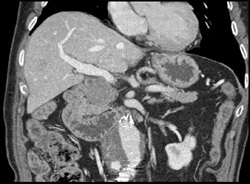

Normal Femoral and Popliteal Arteries